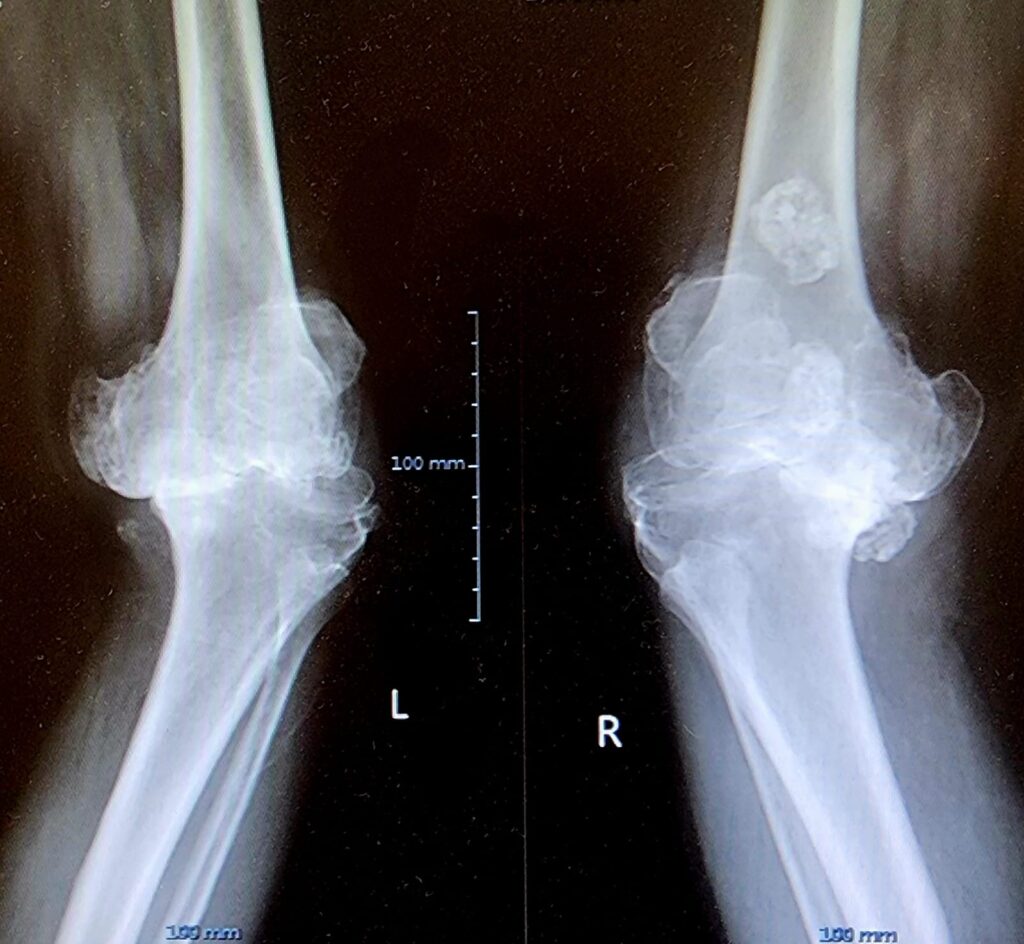

The pre-operative X-rays showed:

• Severe joint space narrowing

• Bone-on-bone contact

• Significant deformity in both knees

These findings confirmed end-stage arthritis, leaving surgery as the best option for restoring function.